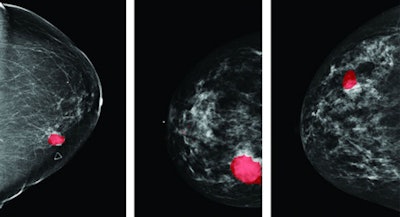

| Three cases of the highlighting of tumors in an x-ray mammogram by using speed of sound thresholds. Data provided by the Karmanos Cancer Institute and Delphinus Medical Technologies. |

To evaluate the accuracy of this method, they compared breast lesion location as defined by the two imaging modalities in 15 clinical datasets. With fully automated registration, the mean displacement of the lesion center was 12.8 mm and the mean lesion overlap was 83%. Using manual corrections to account for patient positioning, the mean displacement reduced to 7.1 mm while the mean overlap increased to 91%. "The speed of sound overlays line up well with lesions that are visible in mammography," said Hopp.

The researchers have developed a semitransparent overlay to display the maximum intensity projection of the deformed speed of sound image directly on the mammogram. This should enable effective visualization of speed of sound properties, and thus breast tissue type. Over the 15 datasets, the mean speed of sound threshold required to distinguish the lesion from surrounding tissue was 1,520 m/sec. "We can distinguish the lesion and surrounding tissue in all cases," said Hopp.

He also noted that changing the threshold value enables different tissue types to be distinguished, with approximate thresholds of 1,350 to 1,450 m/sec highlighting fatty tissue, 1,450 to 1,500 m/sec highlighting glandular tissue, and above 1,500 m/sec visualizing tumor.